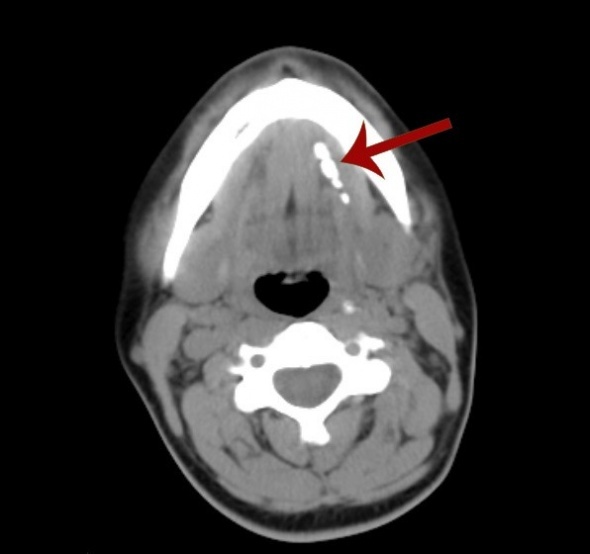

Ameliyat olmaya karar veren Özlem Gül, Medical Park Tarsus Hastanesi’ne gitti. Hastayı muayene eden Kulak Burun Boğaz Hastalıkları Uzmanı Op. Dr. Ali Kahlıoğulları, ameliyatın çene altından girilerek yapılması halinde komplikasyon riskinin olabileceğini ve tükürük bezinin zarar görme riski bulunduğunu belirterek, ağız içinden girilmesi yoluyla operasyonu yapmayı önerdi. Özlem Gül’ün kabul etmesi üzerine Op. Dr. Kahlıoğulları ve ekibi, mikrocerrahi tekniğiyle ve mikroskop altında operasyonu gerçekleştirdi. Ameliyatta, tükürük bezinden ikisi 8 mm çapında, ikisi ise 2 mm çapında olmak üzere toplam 4 taş çıkarıldı. Tükürük bezi ise ameliyattan zarar görmedi.